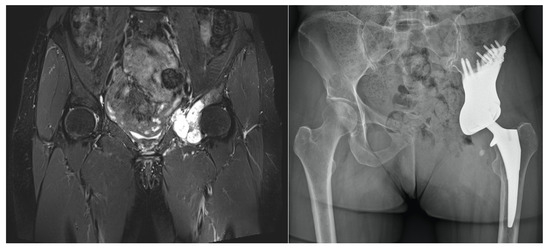

| Aseptic loosening | 4 | 38.5 (10–80) months |

| Dislocation | 3 | 5 months (14 days–20 months) |

| Sciatic nerve lesions | 4 | 26 (24–28) months |